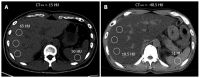

Nonalcoholic fatty liver disease (NAFLD) is a frequent cause of chronic liver diseases, ranging from simple steatosis to nonalcoholic steatohepatitis (NASH)-related liver cirrhosis. Although liver biopsy is still the gold standard for the diagnosis of NAFLD, especially for the diagnosis of NASH, imaging methods have been increasingly accepted as noninvasive alternatives to liver biopsy. Ultrasonography is a well-established and cost-effective imaging technique for the diagnosis of hepatic steatosis, especially for screening a large population at risk of NAFLD. Ultrasonography has a reasonable accuracy in detecting moderate-to-severe hepatic steatosis although it is less accurate for detecting mild hepatic steatosis, operator-dependent, and rather qualitative. Computed tomography is not appropriate for general population assessment of hepatic steatosis given its inaccuracy in detecting mild hepatic steatosis and potential radiation hazard. However, computed tomography may be effective in specific clinical situations, such as evaluation of donor candidates for hepatic transplantation. Magnetic resonance spectroscopy and magnetic resonance imaging are now regarded as the most accurate practical methods of measuring liver fat in clinical practice, especially for longitudinal follow-up of patients with NAFLD. Ultrasound elastography and magnetic resonance elastography are increasingly used to evaluate the degree of liver fibrosis in patients with NAFLD and to differentiate NASH from simple steatosis. This article will review current imaging methods used to evaluate hepatic steatosis, including the diagnostic accuracy, limitations, and practical applicability of each method. It will also briefly describe the potential role of elastography techniques in the evaluation of patients with NAFLD.